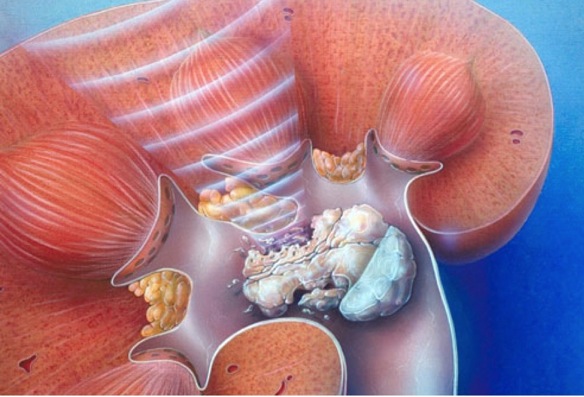

La cirugía abierta o laparoscópica se reserva solo a los casos más complejos, con litiasis de gran tamaño que ocupan gran parte del riñón.